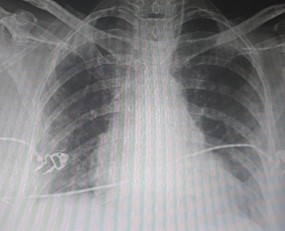

Severe Disease

X ray On Discharge